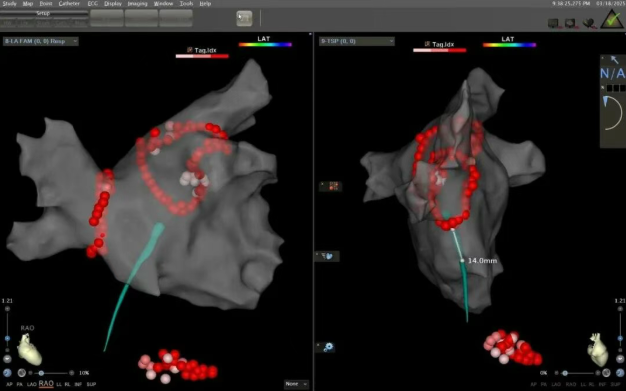

近日我院张奇峰教授团队通过磁导航导管完成三例零射线消融术,单次房间隔穿刺缩短时间至5分钟以内,整体手术时间控制在2个小时以内,术后患者均无并发症。

更精准:三维超声联合标测系统可将心脏三维建模误差控制在小于1毫米,提升消融效率,降低复发。